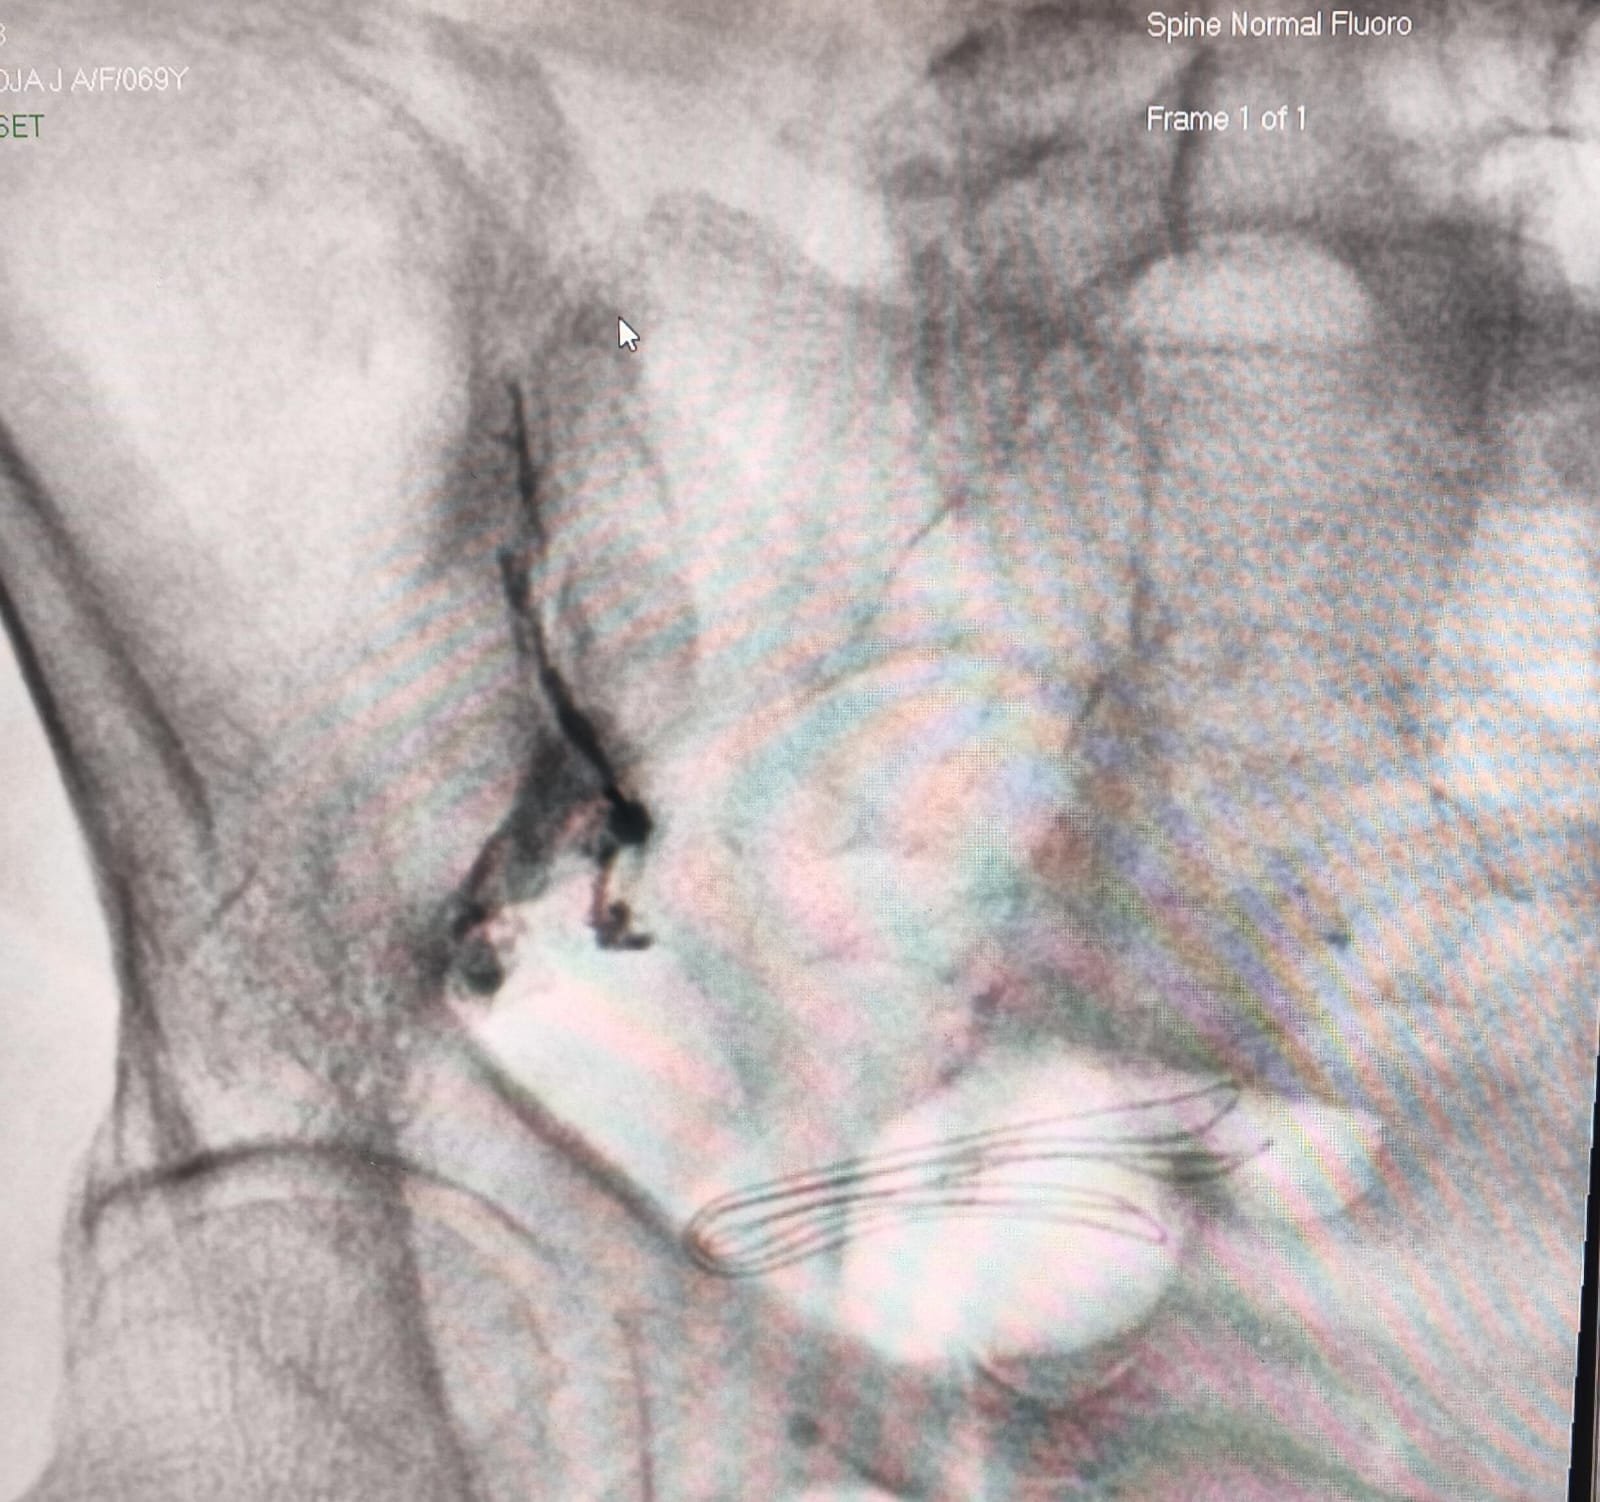

• Imaging-guided targeting: Fluoroscopy or ultrasound helps the doctor visualize the exact structure causing pain.

• Precise treatment delivery: Medication to reduce inflammation,Heat energy for nerve ablation (RFA), Electrical stimulation (nerve modulation)